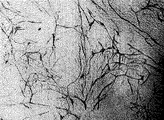

- 238000001000 micrograph Methods 0.000 description 3